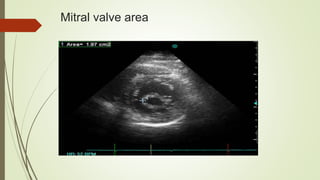

Mitral valve area